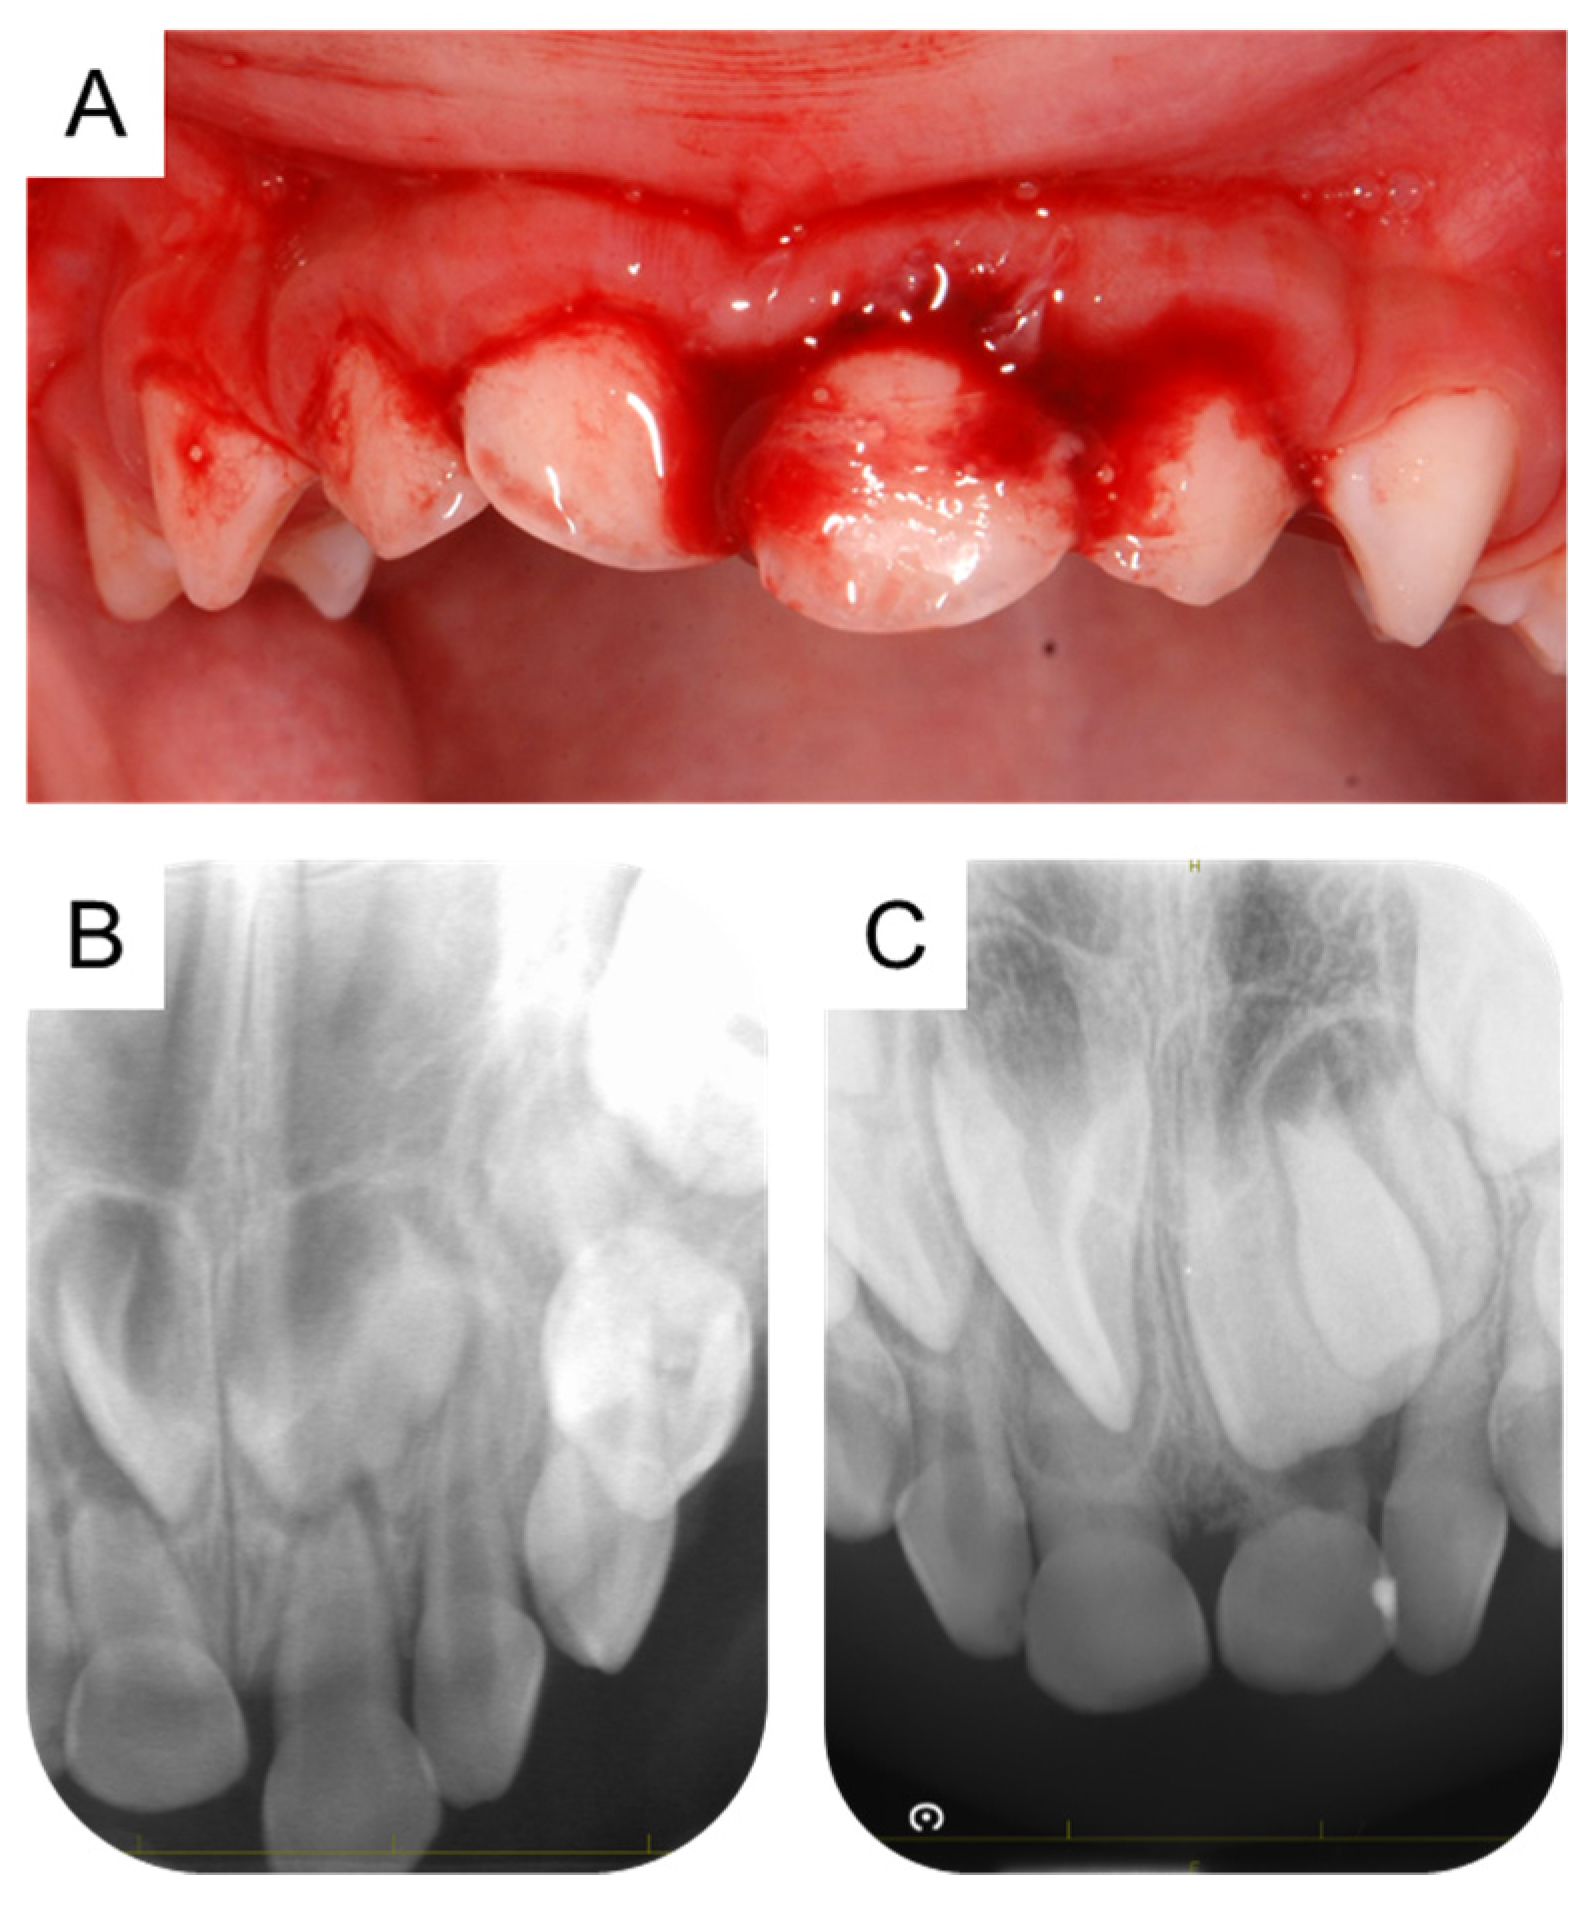

2. Case Presentation

5.2. The Present Case